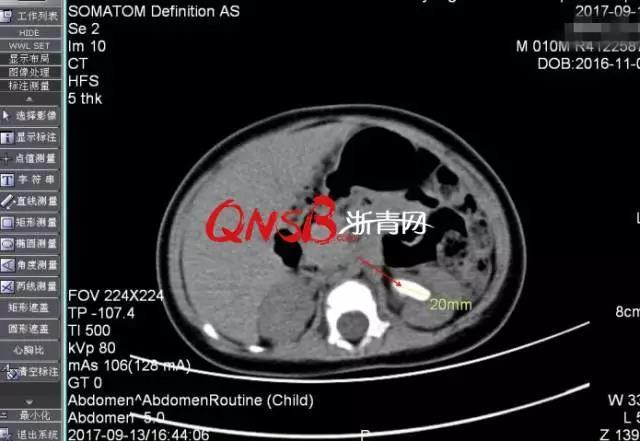

Kết quả thăm khám đã khiến bác sỹ và cả gia đình phải ngạc nhiên khi nhận thấy một viên sỏi đường kính 2cm đang nằm trong thận của Tiểu Ái, đường niệu quản thì bị giãn. Thế là em phải chuyển đến bệnh viện lớn hơn để điều trị vì kích thước viên sỏi quá lớn so với một em bé 10 tháng tuổi. e